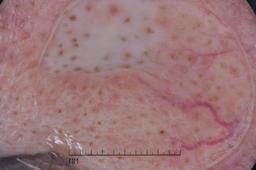

ISIC-DICM-17K (ISIC Dermoscopic Images and Clinical Metadata 17K) is a curated and balanced dataset derived from the International Skin Imaging Collaboration (ISIC) Archive Gallery. It comprises 17,060 dermoscopic images and clinical metadata (8,530 melanoma and 8,530 non-melanoma classes).

For more details, please follow the project’s GitHub repository: https://github.com/mmu-dermatology-research/isic-dicm-17k

This dataset was used in this study and benchmark to explore the effectiveness of multimodal learning for skin lesion classification:

S. Ahammed, X. Cui, W. Lu and M. H. Yap, "Skin Lesion Classification using Dermoscopic Images and Clinical Metadata: Insights from Multimodal Models," 2025 IEEE/CVF Conference on Computer Vision and Pattern Recognition Workshops (CVPRW), Nashville, TN, USA, 2025, pp. 222-230, DOI: 10.1109/CVPRW67362.2025.00027